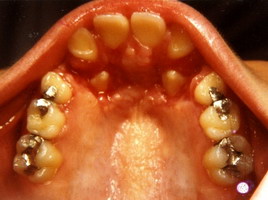

Τελική Κατάσταση